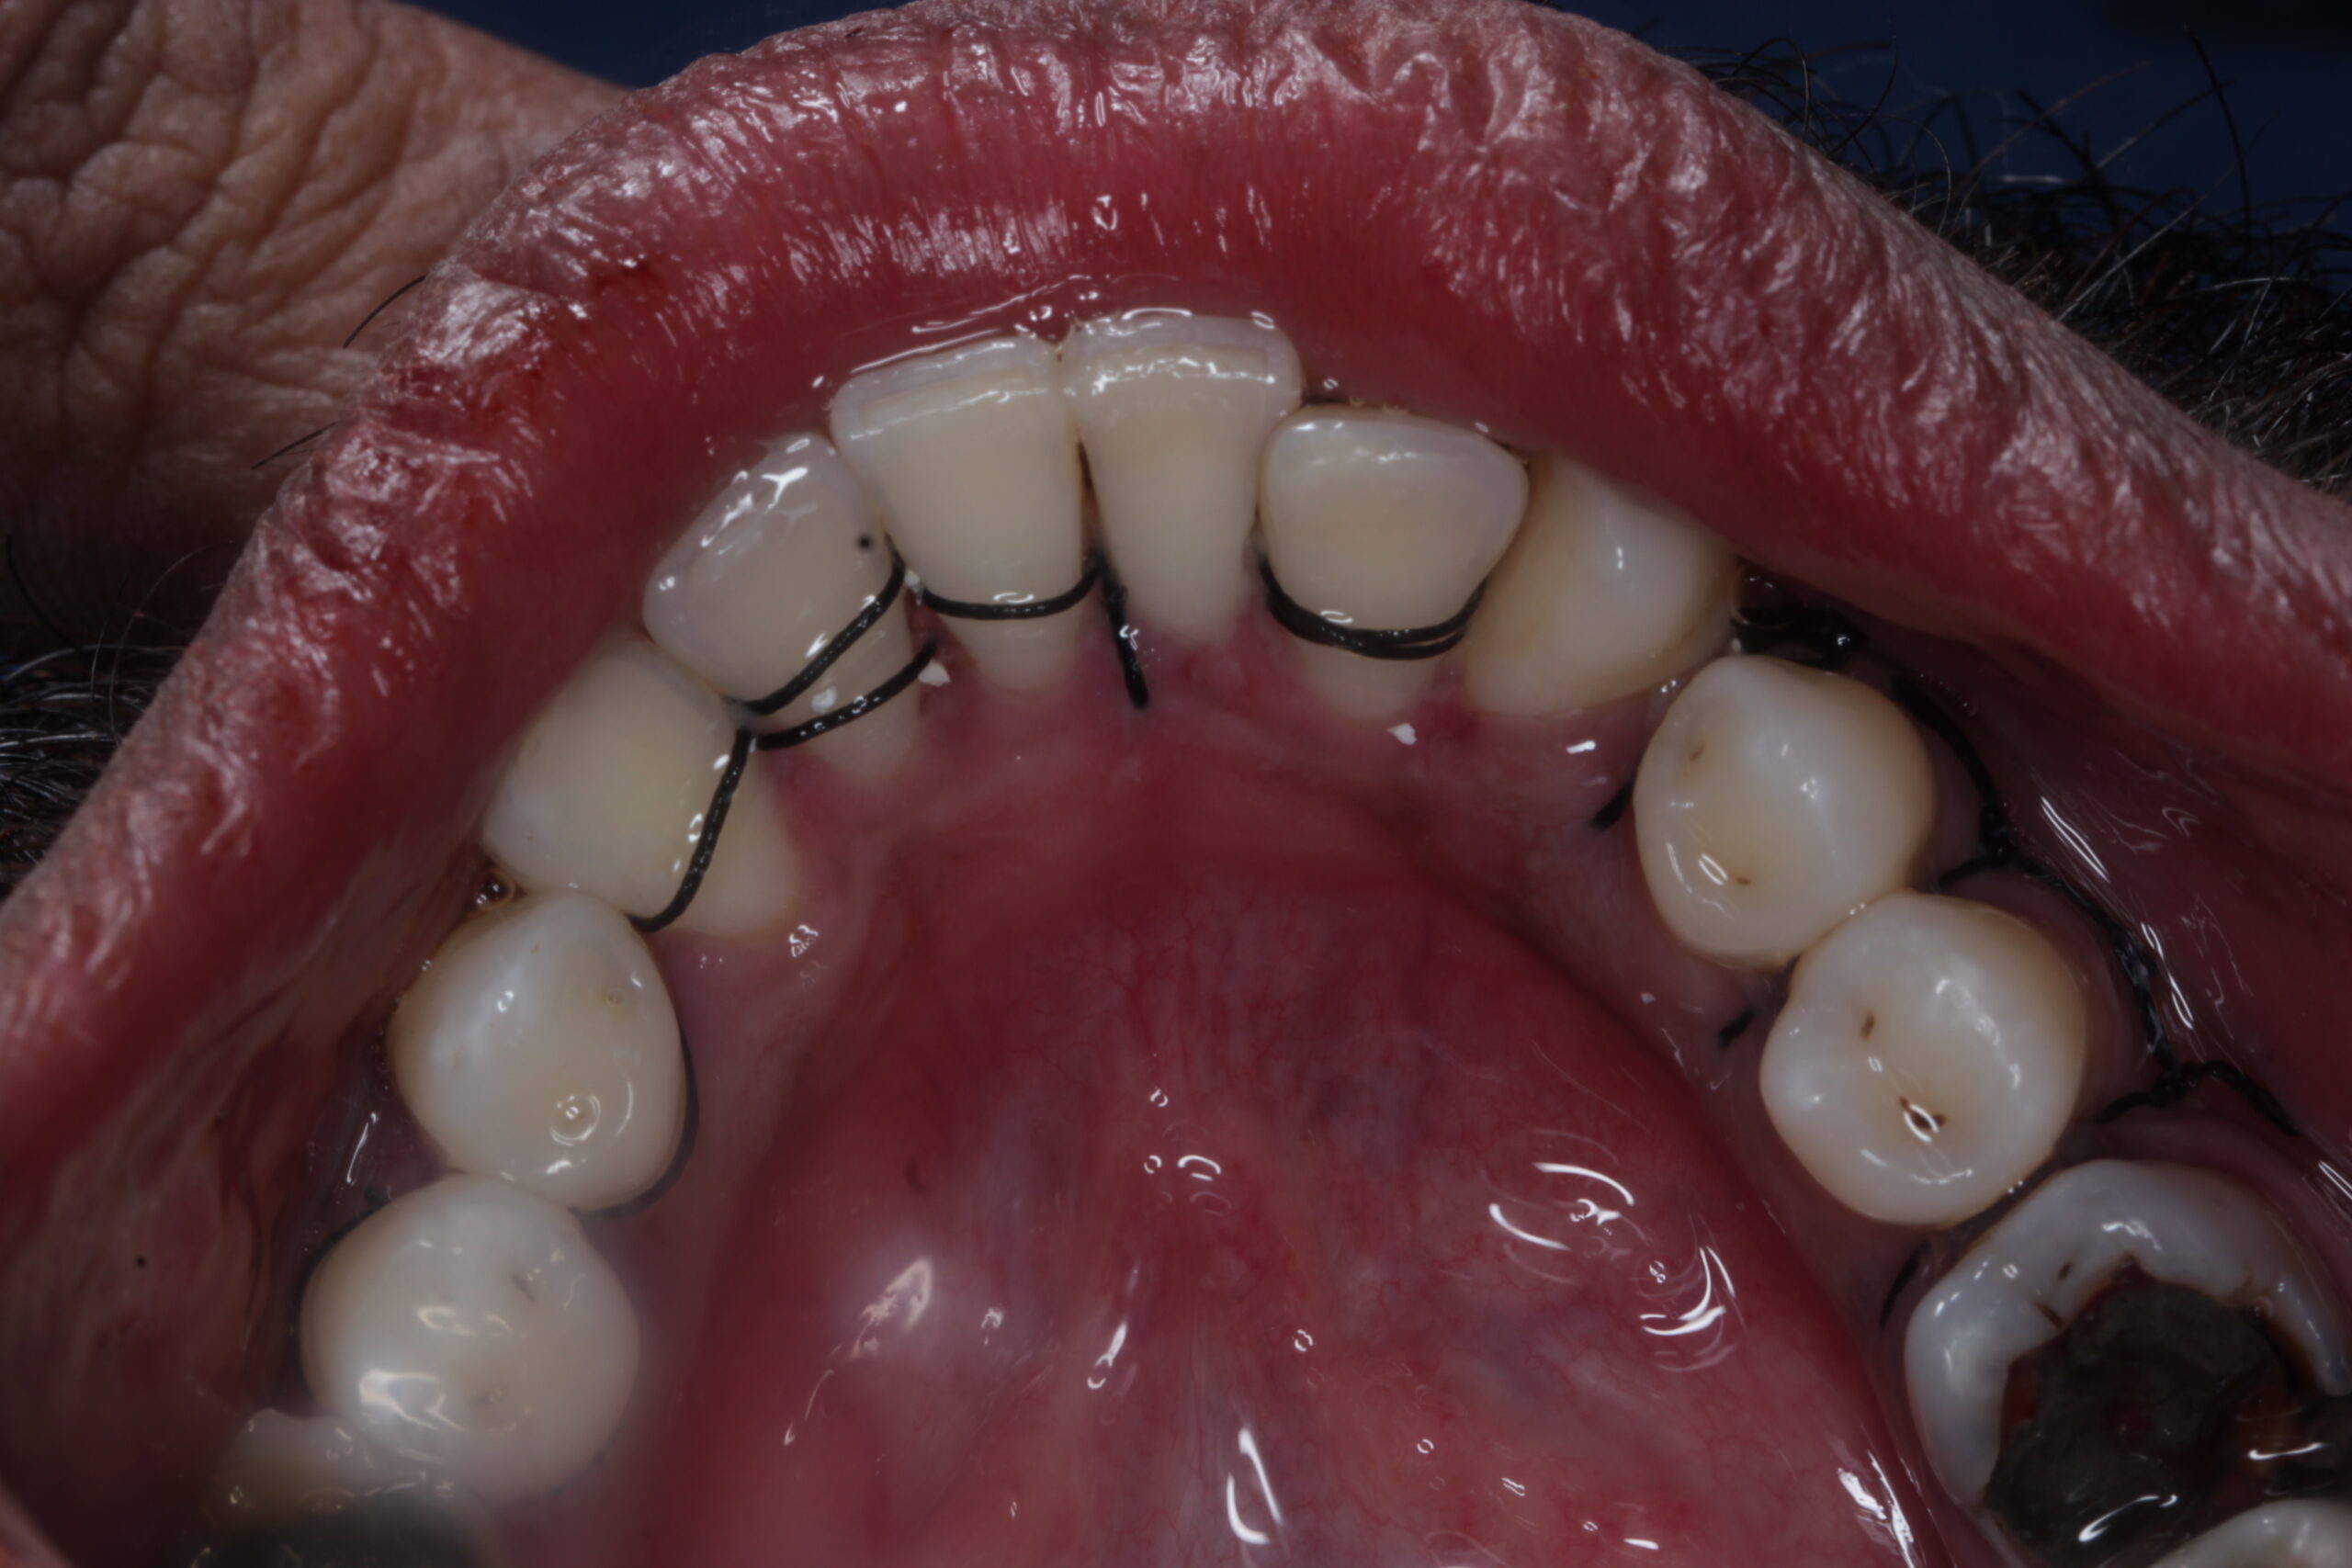

• Repositioning the Gums: After cleaning, the gums are placed back in position and sutured to fit snugly around the teeth.

• Post-Surgery Recovery: Post-operative care instructions are given to prevent infection and ensure proper healing.

• Prevention of Further Gum Disease: By thoroughly cleaning the roots, the procedure helps to eliminate infection, preventing further gum loss.

• Long-Term Health Benefits: After the procedure, the gums are typically healthier, and the risk of tooth loss is greatly reduced.